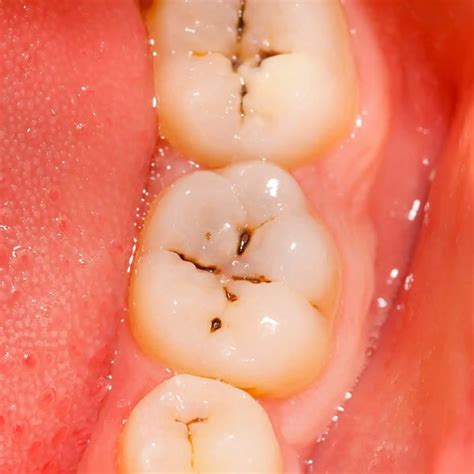

Stage 2: Enamel Decay

If the demineralization process continues unchecked, the enamel will eventually break down. Once the surface is compromised, the cavity can no longer be reversed. This stage is characterized by the white spots turning into a brownish color. You may not feel pain yet because the decay has not reached the inner layers of the tooth where the nerves reside. It is crucial to visit a dentist at this point so that a simple dental filling can stop the progression.